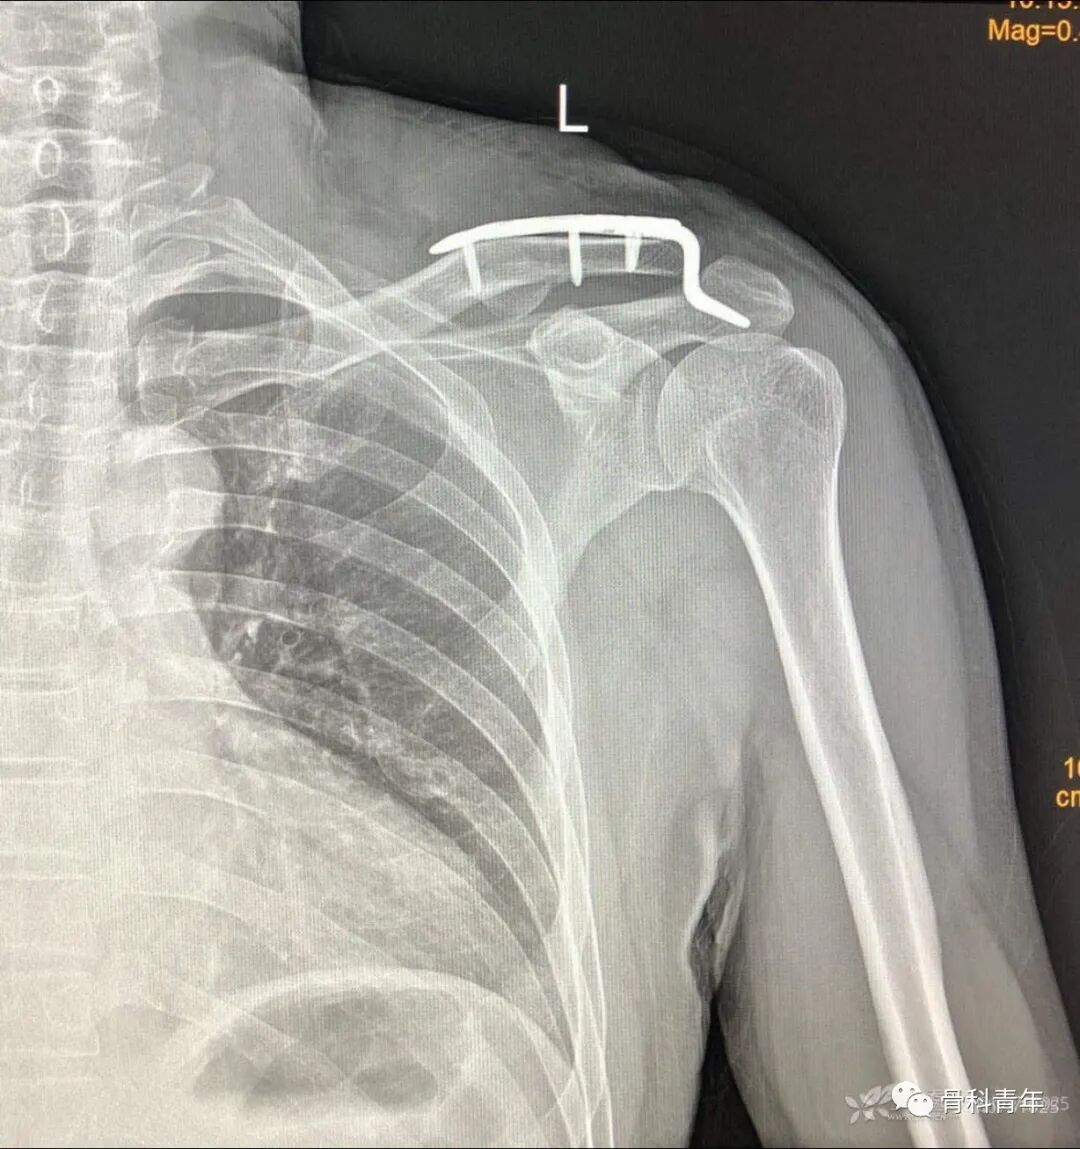

21.肩锁关节脱位